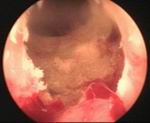

Prostatic enlargement is a comman problem is old age. By TURP nearly all patient who requires surgery for prostate can be treated successfully without any incision. Under anesthesia per urethral scope is inserted & under vision prostate is resected. Patient requires 2 to 4 days hospitalization & 1 week rest. Usually patient does not requires blood transfusion & patient can tolerate endoscopic surgery very well without risk of incontinance of urine.